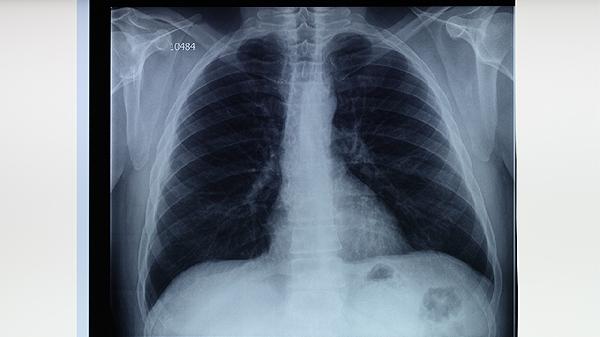

肺結(jié)核患者應(yīng)保證每日充足睡眠,避免過度勞累。居室保持通風(fēng)良好,每日開窗換氣2-3次。適當(dāng)進行散步、太極拳等溫和運動,增強體質(zhì)但避免劇烈活動。嚴(yán)格遵醫(yī)囑完成6-8個月規(guī)范治療,不可自行停藥。定期復(fù)查胸部X線片和痰菌檢查,密切觀察藥物不良反應(yīng)。注意與家人分餐,咳嗽噴嚏時遮掩口鼻,痰液需消毒處理。保持樂觀心態(tài),積極配合治療有助于早日康復(fù)。